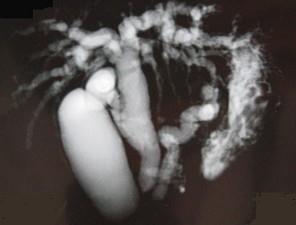

问题 患者男,47岁,进行性黄疸,发热,腹胀,影像检查如图,最可能的诊断是 ( )

选项 A、十二指肠壶腹癌 B、胰头癌 C、胆总管结石 D、胆总管癌 E、胆总管囊肿

答案 A